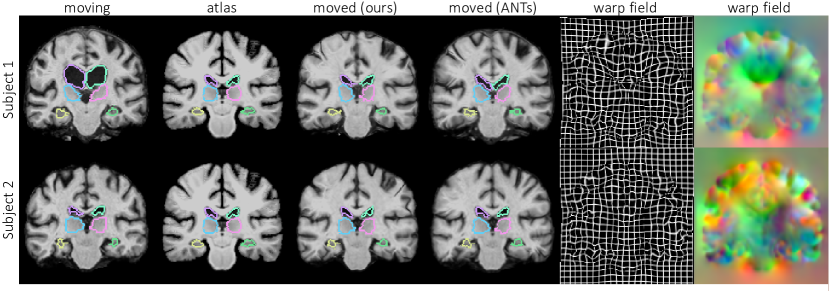

Refer to caption

Figure 2: Example MR slices of input moving image, atlas, and resulting warped image for our method and ANTs, with overlaid boundaries of ventricles, thalami and hippocampi. Our resulting registration field is shown as a warped grid and RGB image, with each channel representing dimension. Due to space constraints, we omit VoxelMorph examples, which are visually similar to our results and ANTs.

Results on Test set: Figure 2 shows representative results. Figure 3 illustrates Dice results on a range of anatomical structures, and Table 1 gives a summary of the results. Not only does our algorithm achieve state of the art Dice results and the fastest runtimes, but it also produces diffeomorphic registration fields (having nearly no non-negative Jacobian voxels per scan) and yields uncertainty estimates.